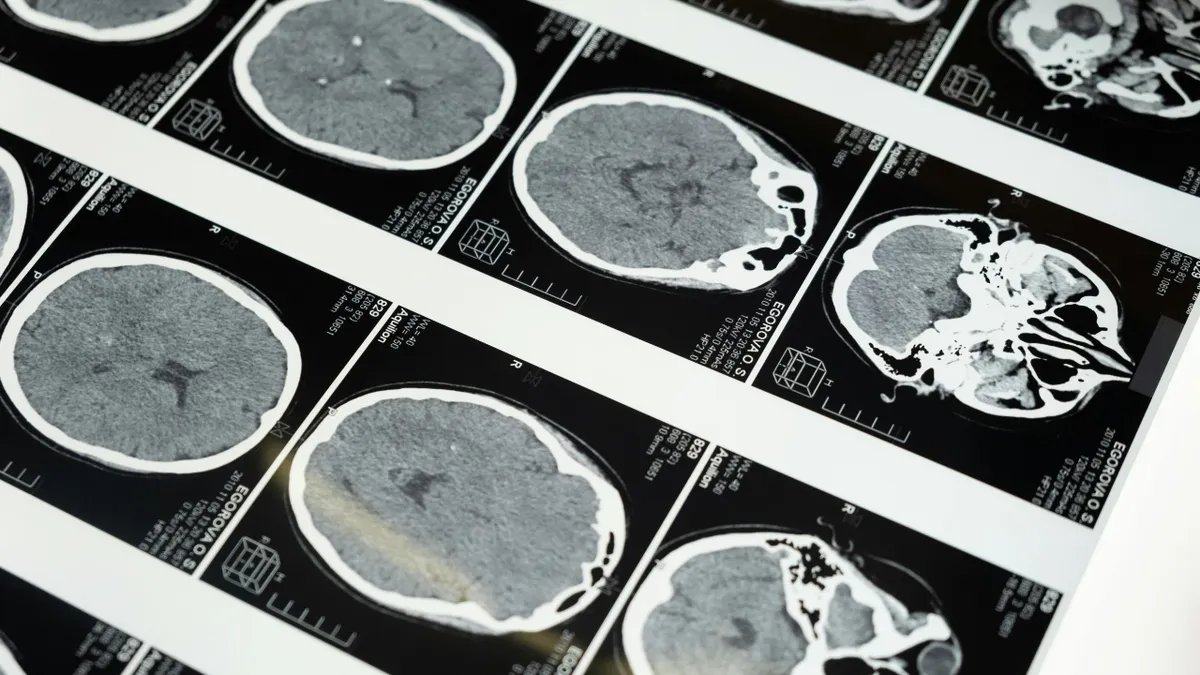

A imagem cerebral destaca as regiões que os pesquisadores estudam à medida que as empresas exploram a tecnologia de interface cérebro-computador de ultrassom não invasivo. (Kurt “CyberGuy” Knutsson)